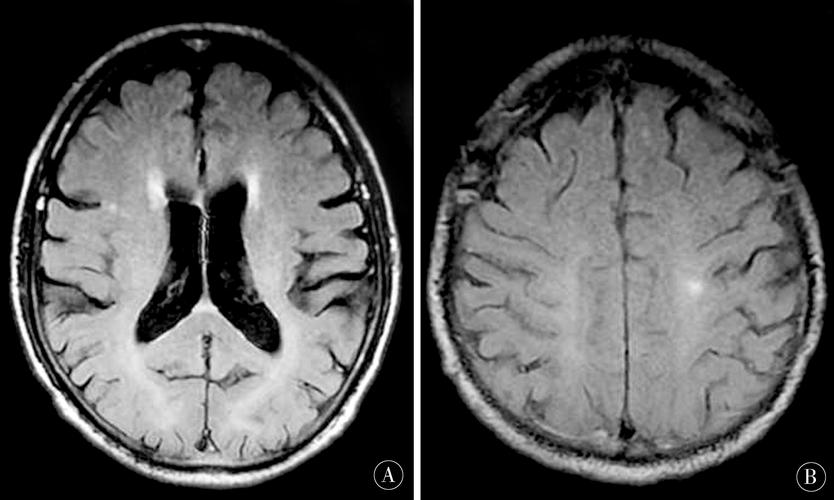

急性期(6小时 - 3天)

这是MRI最容易发现病灶的时期。

(图片来源网络,侵删)

- DWI:病灶仍呈明显高信号,弥散受限达到顶峰。

- ADC:持续呈低信号。

- T2加权像:病灶开始出现高信号。

- FLAIR(液体衰减反转恢复)序列:对显示靠近脑脊液(如脑室、脑沟)的病灶非常敏感,病灶呈明显高信号,且比T2更清晰,因为脑脊液信号被抑制了。

- T1加权像:病灶通常呈等信号或低信号,此时可能不明显。

小结:急性期,DWI高信号和T2/FLAIR高信号是主要表现。